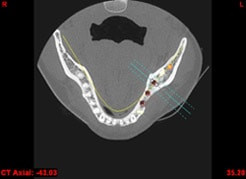

In komplexen Fällen, z. B. der Implantatversorgung eines kompletten Kiefers, oder bei schwierigen Knochensituationen bietet die 3-dimensionale Computerdiagnostik bzw. Planung und Durchführung erhebliche Vorteile und Sicherheit für den Patienten (siehe Bild 1 und 2).

Computerdarstellung des Kiefers mit geplanter Implantatposition

Auf Basis einer computertomografischen (CT-) Kieferaufnahme ist eine dreidimensionale Darstellung der Knochen möglich. Der Zahnarzt kann dann am Computerbildschirm die Knochenqualität (z. B. Knochendichte) beurteilen und die optimale Position der Implantate im Vorfeld planen. Durch Verwendung spezieller Röntgenschablonen lässt sich auch die erwünschte Zahnstellung in die Planung einbeziehen. Die Simulation der OP erlaubt, das zu erwartende Ergebnis mit größtmöglicher Sicherheit vorherzusagen und dem Patienten am Bildschirm zu veranschaulichen.

(siehe Bild 3 und 4).